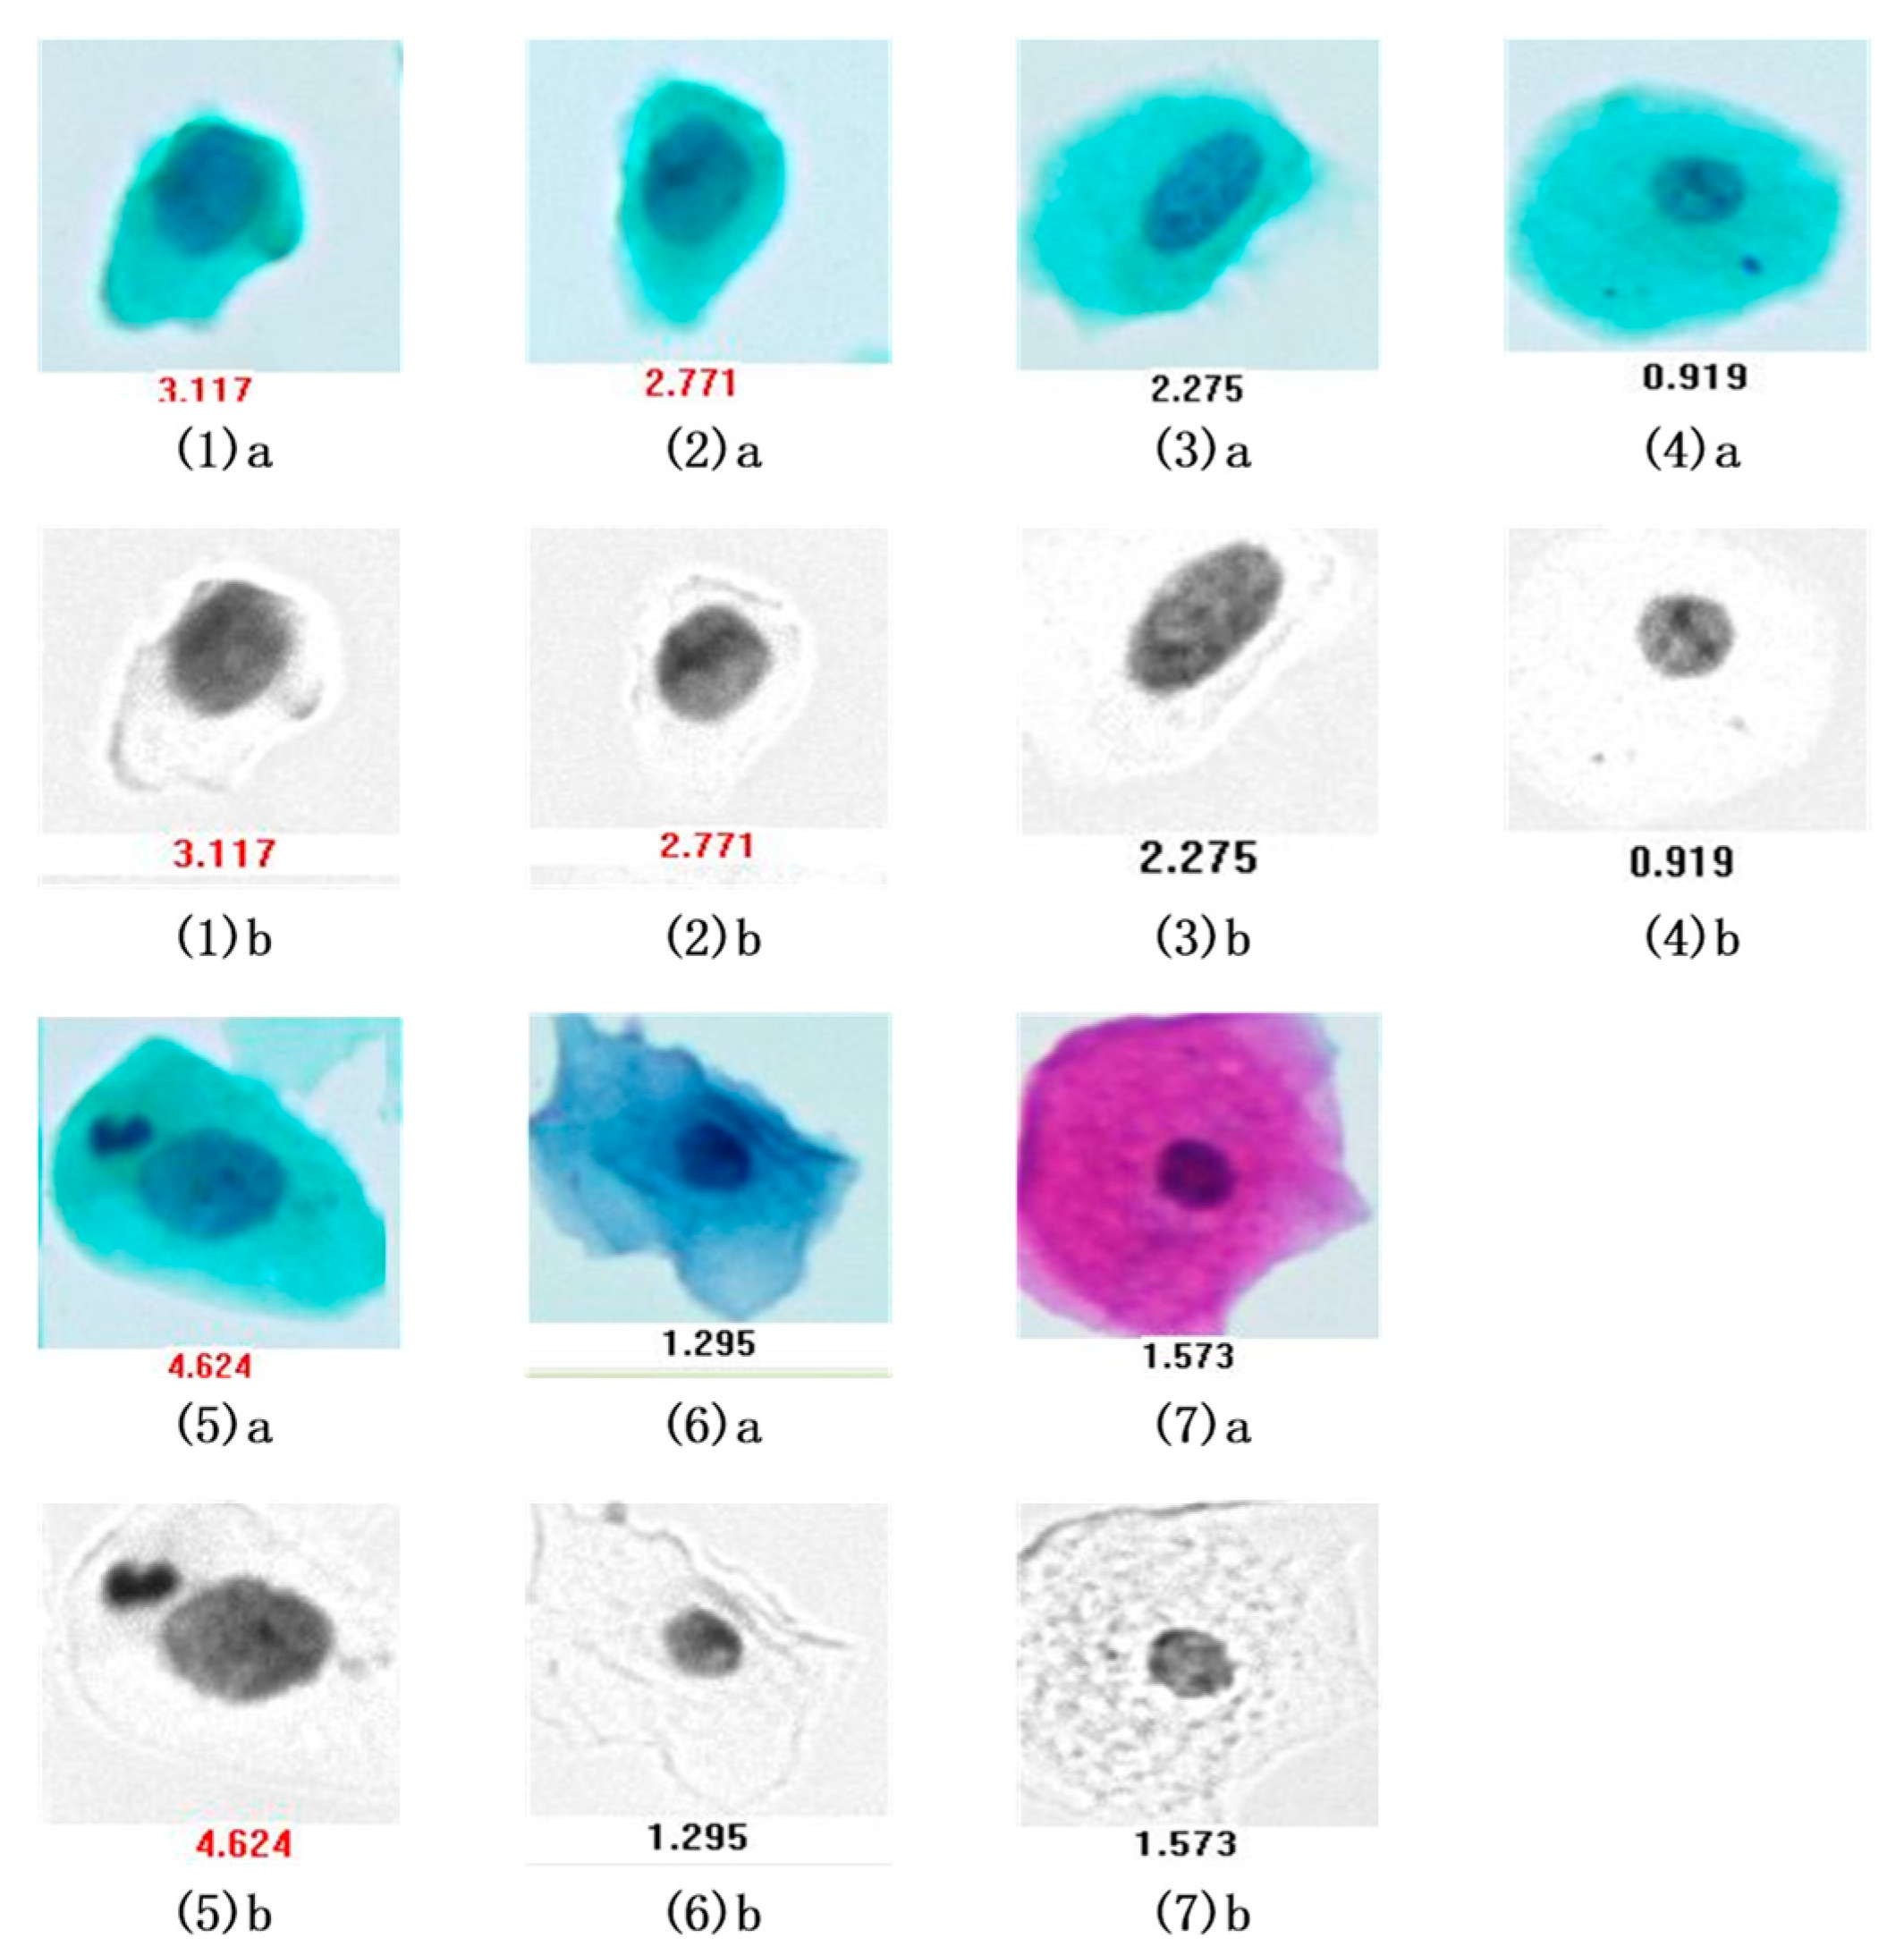

3.1. Pseudo-Color Image Synthesizing and Absorbance Unmixing